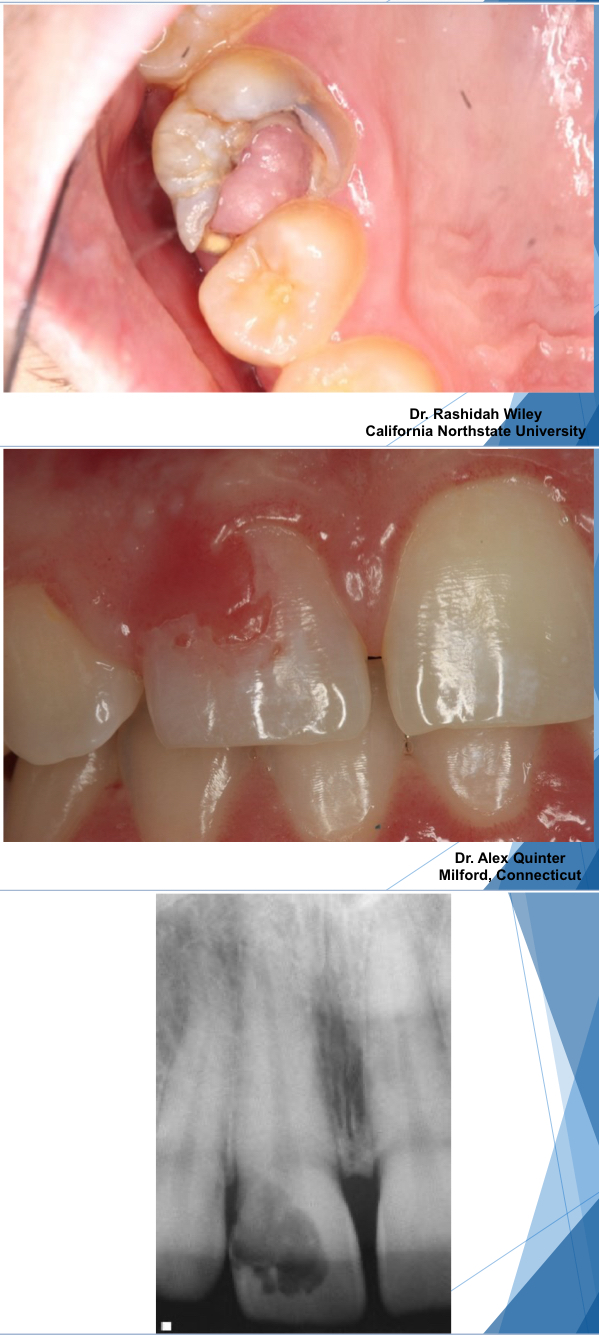

what is chronic hyperplastic pulpitis?

pulp polypÂ

unique pattern of pulpitis sometimes seen in children and young adults w large pulp exposures (usually primary molars)

hyperplastic granulation tissue extrudes from pulp chamber

asymptomaticÂ

chronic hyperplastic pulpitis usually affects (primary) molars

treatment of chronic hyperplastic pulpitis?

endo or extraction

chronic hyperplastic pulpitis